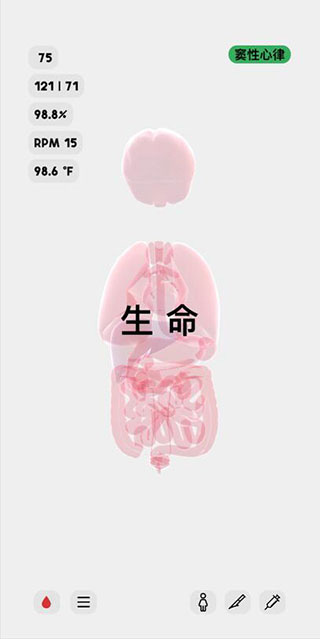

2、这时候我们可以看到人体模型已经成功创建,显示的是人体各个器官的透视图,左上角显示是人体的各个主要信息参数指标。

8、屏幕右上角显示的是该人体模型的异常状态,例如现在,她正处于低血钾和低血糖的状态中。